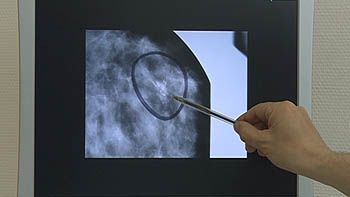

Este es el hallazgo de un estudio de ámbito nacional que ha liderado un grupo de investigación del Instituto de Biología y Genética Molecular (IBGM) de la Universidad de Valladolid. La importancia de este hallazgo radica en que los resultados podrán ser de gran ayuda a la hora del diagnóstico precoz de la predisposición genética al cáncer de mama y de ovario, ya que aproximadamente un 10% de este tipo de cáncer es hereditario.

Los dos principales genes que predisponen a esta enfermedad, BRCA1 y BRCA2, son responsables del 20% del cáncer de mama hereditario y presentan más de 3.500 variantes de ADN distintas, es decir, es complicado encontrar una mutación prevalente que aparezca en varias familias.

La mutación, sin embargo, en la que se ha basado este estudio (conocida como 3036delACAA) es la más frecuente en Castilla y León- más del 18% son familias portadoras de esta mutación- y es una de las más frecuentes en España y la segunda más referida en las bases de datos internacionales. Para el estudio se han utilizado muestras de 51 familias portadores de toda España.